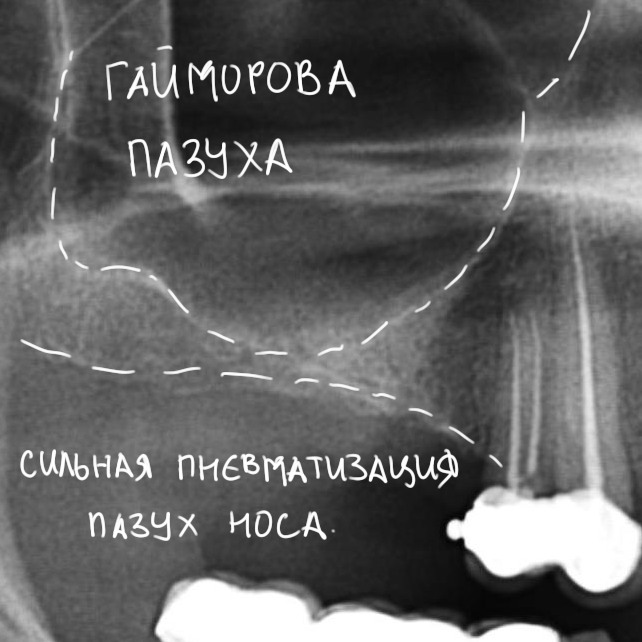

Все разные, у каждого из нас есть особенности анатомического строения, делающие его непохожим на других людей. Применительно к теме нашей беседы, можно сказать, что гайморова пазуха при одинаковом внешнем объеме верхней челюсти, у разных пациентов может быть разного размера: у кого-то она очень большая и воздушная (т. н. «гиперпневматизация»), у кого-то, наоборот – маленькая и склерозированная («гипопневматизация»). Это индивидуальная анатомическая особенность. К примеру, на рисунках 3 и 4 представлены ортопантомограммы двух пациентов одного возраста и пола с похожими клиническими случаями. На рисунке 3 мы видим небольшого размера верхнечелюстную пазуху (обозначена черной пунктирной линией), в то время как на рисунке 4 – выраженная гиперпневматизация верхнечелюстной пазухи (границы верхнечелюстной полости обозначены белой пунктирной линией).

Рисунок 3, 4. Расположение и объем гайморовой пазухи – индивидуальная анатомическая особенность. Слева – гипо-, а слева – гиперпневматизация придаточных пазух носа.

Большая и гиперпневматизированная гайморова пазуха почти всегда является показанием к проведению синуслифтинга, поскольку занимает большую часть, в том числе, и альвеолярного отростка.